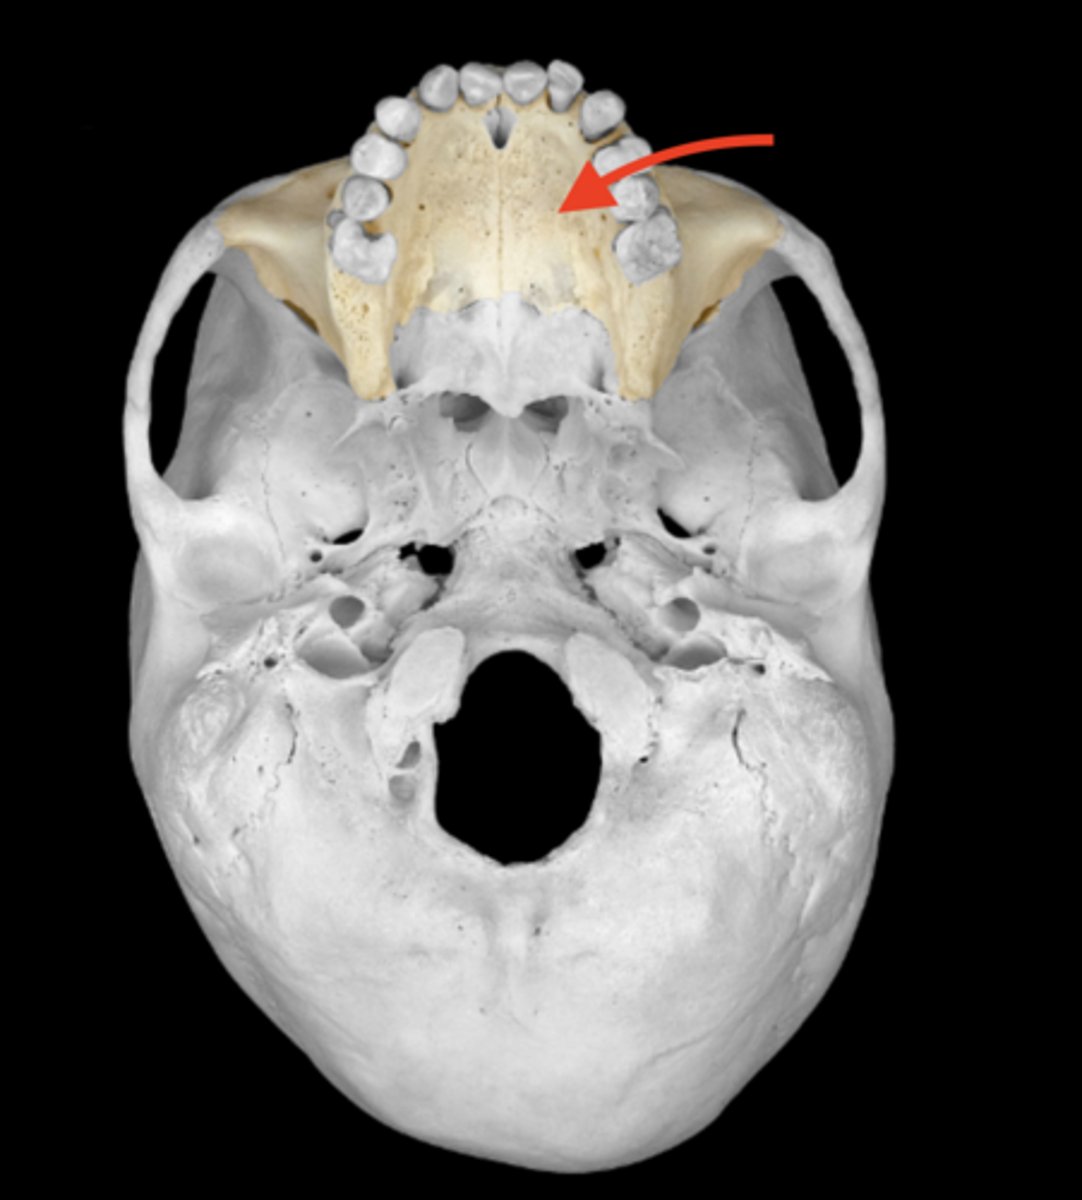

palatine processes of the hard palate of maxillae

intermaxillary suture of maxillae

median palatine suture of maxillae

incisive fossa of median palatine suture of maxillae

transverse palatine suture of maxillae

alveolar process of maxillae

dental alveoli of the maxilla